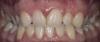

bugroff87 Опубликовано 22 марта, 2013 Поделиться Опубликовано 22 марта, 2013 Вот такая ситуация, 1.2 отсутствует, ортодонтию не хочет! Ваши предложения... Ссылка на комментарий

bugroff87 Опубликовано 23 марта, 2013 Автор Поделиться Опубликовано 23 марта, 2013 Ее не устраивает ее улыбка, "не ровно расположенные зубы", конечно ясно, что в идеале ортодонтия! Ссылка на комментарий

bugroff87 Опубликовано 23 марта, 2013 Автор Поделиться Опубликовано 23 марта, 2013 Понятно, что в лучшем случае ортодонт! Насколько я понял ее особо не волнует отсутствие двушки, больше положение центральных резцов! Ссылка на комментарий